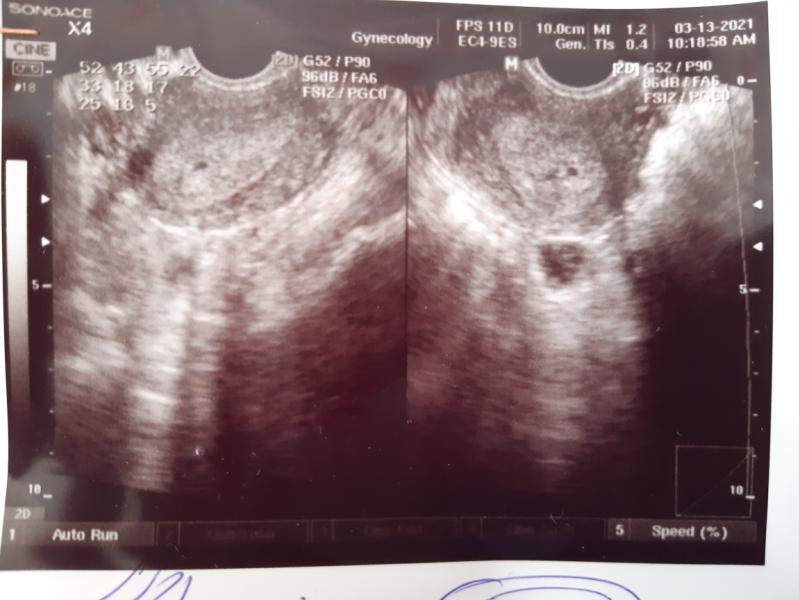

фото УЗИ

13.03.2021

@rasaevat врач сказал 7-8 недель, а размер плодного яйца на 3 недели